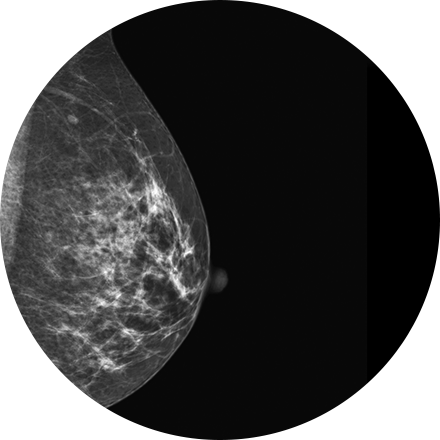

Digital Mammography

Mammography is a type of low-dose X-ray of the breast. It reveals masses and micro-calcifications within and around the breast that may indicate breast problems including, but not just limited to cancer.

Experts recommend a mammography screening of the breasts at regular intervals to increase the chance of early cancer detection and treatment. The American College of Radiology recommends women aged 40 and older should have a screening mammogram every year and should continue to do so for as long as they are in good health.